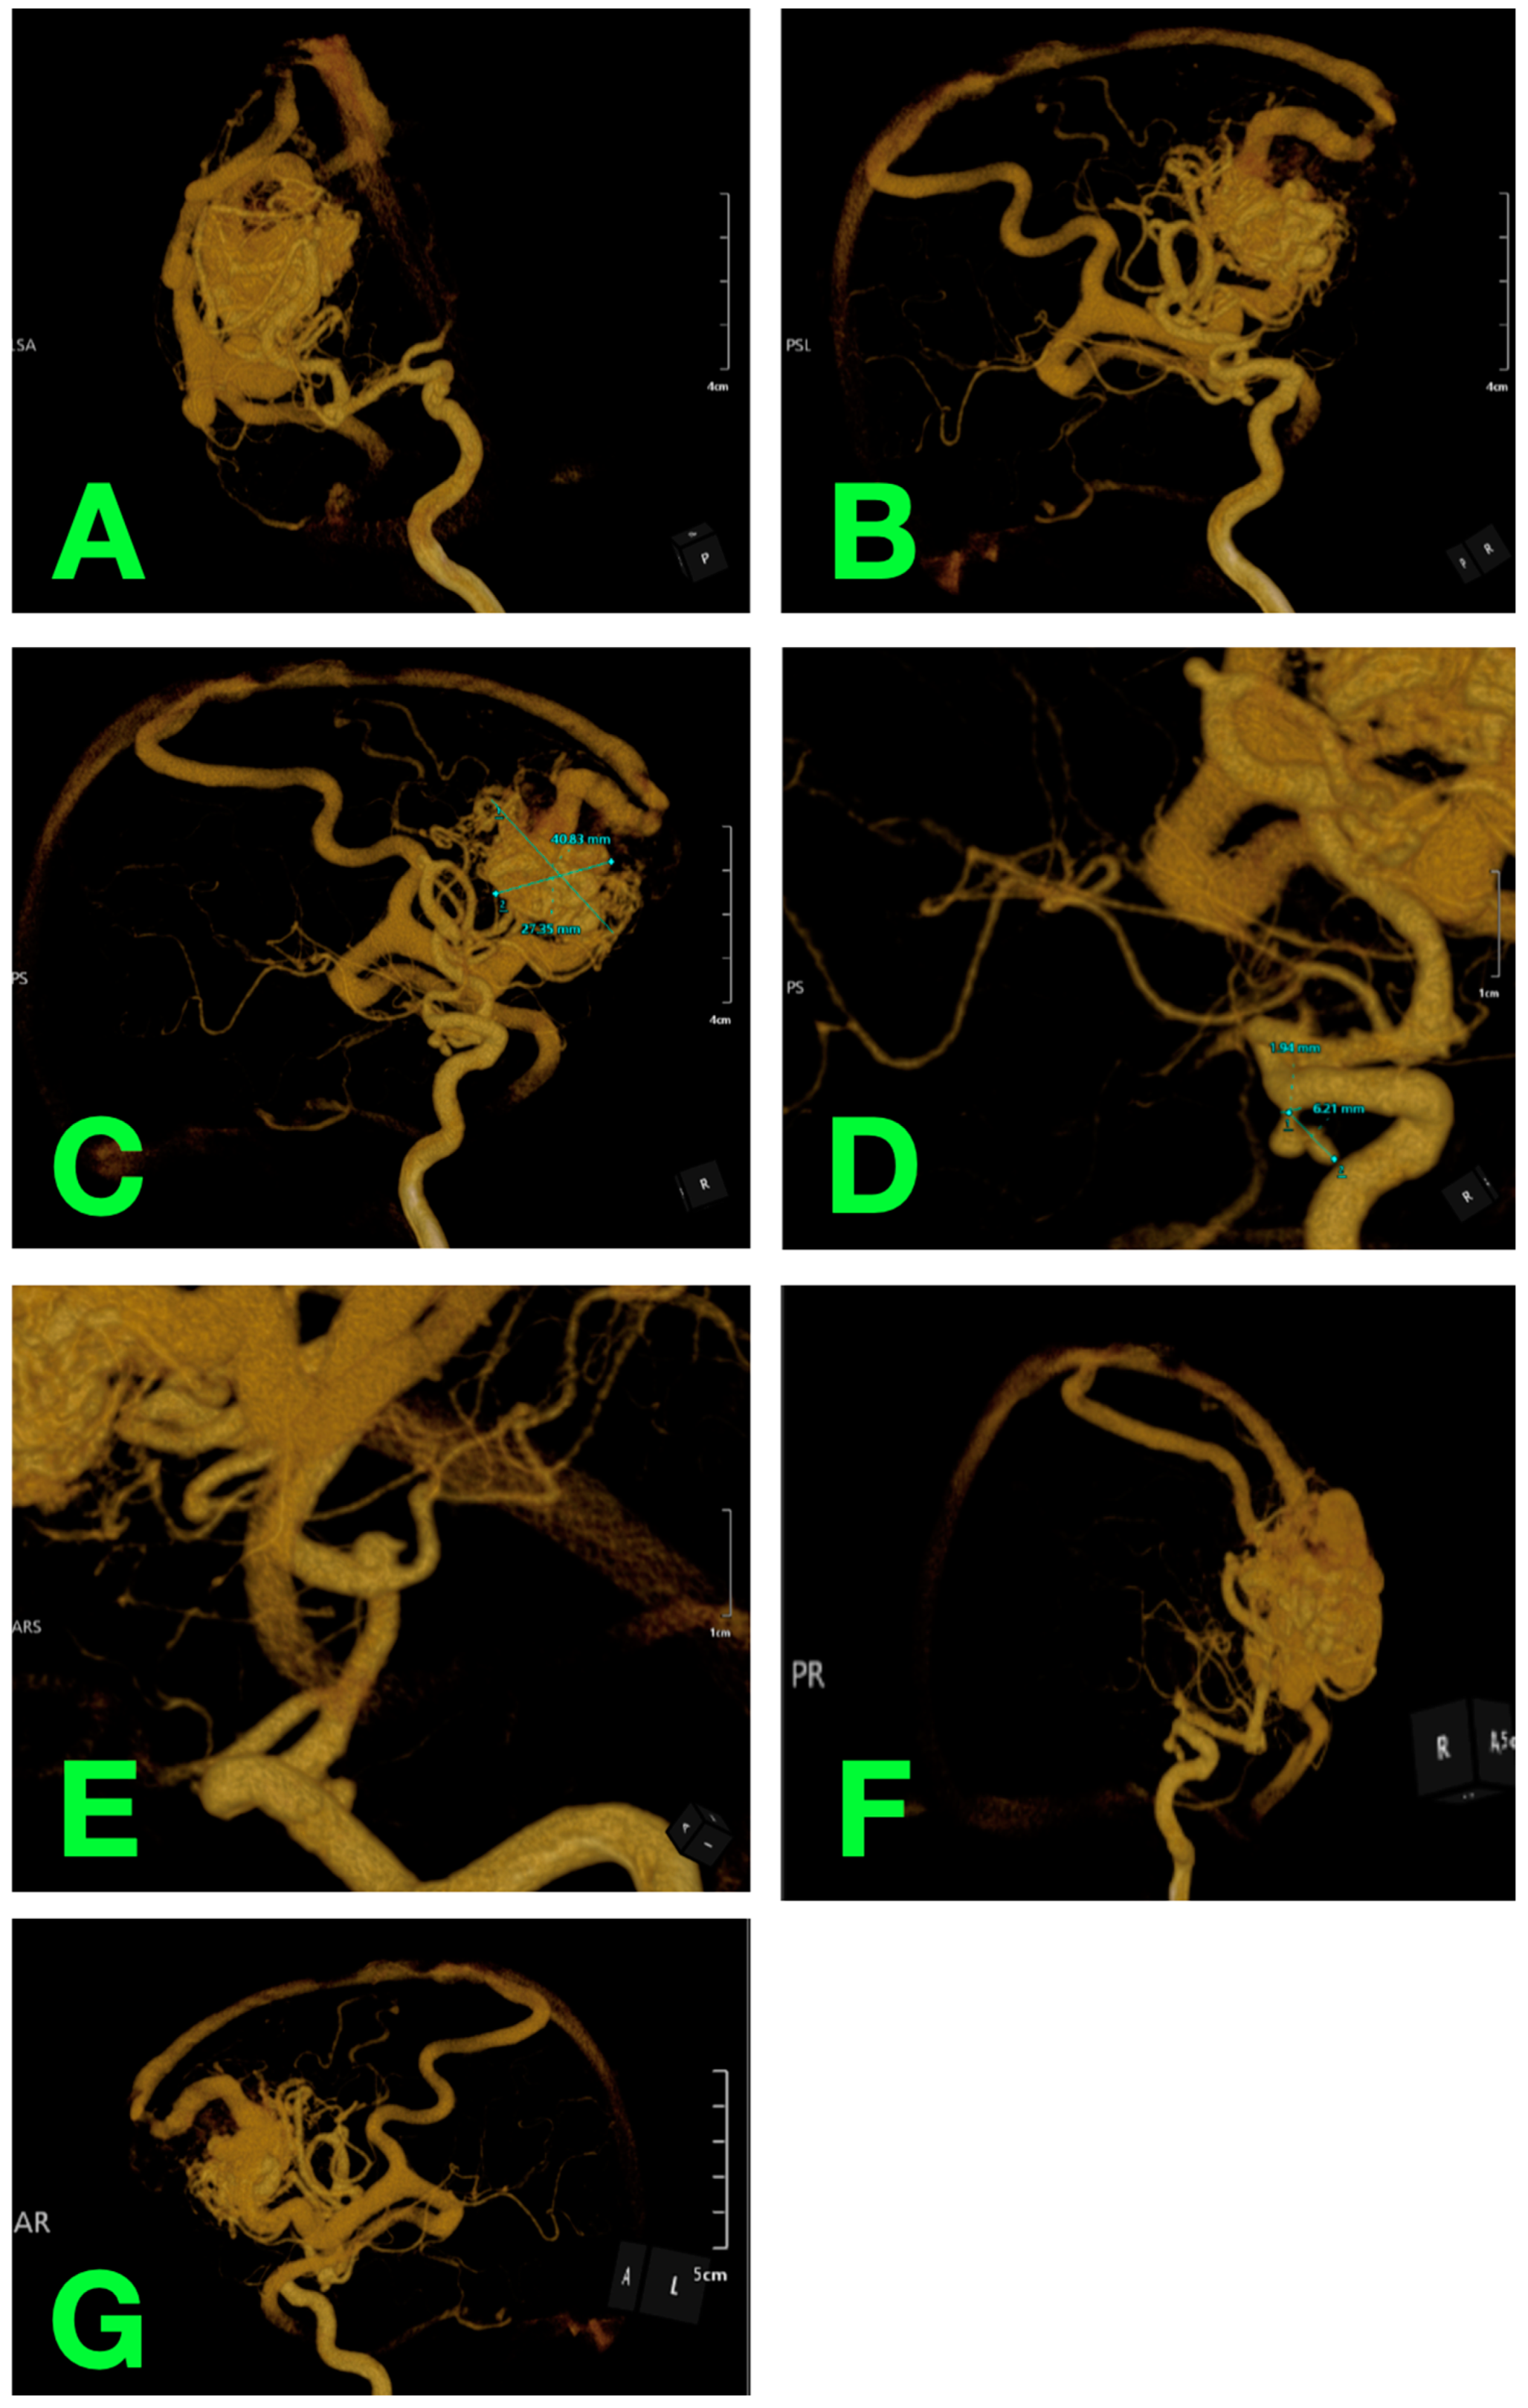

2.2. Diagnostic Workup

2.4. Surgical Intervention